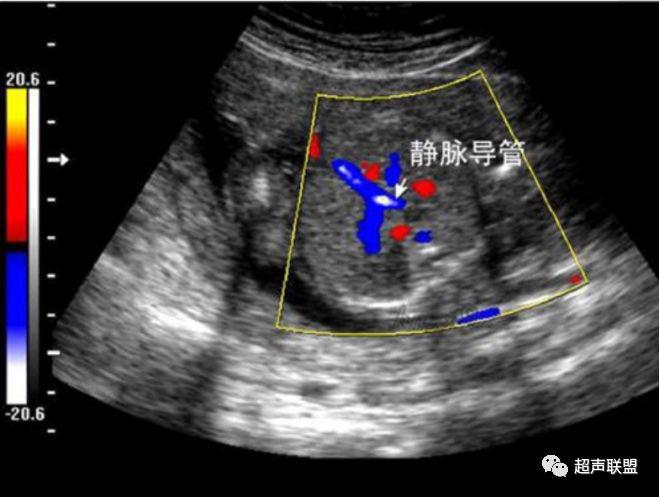

3 胎儿静脉导管

当右心负荷增大,心功能失代偿时,静脉回流受阻,静脉导管a波收缩期流速下降,血流消失甚至倒置。

5、静脉导管:a波消失或反向(见于严重的胎儿宫内缺氧);

7、宫内缺氧时肾动脉及腹主动脉的血流频谱为舒张末期血流的降低,RI及PI值会逐渐升高,若血流再分配严重时其舒张末期的血流将会消失甚至出现反向血流的产生。同时静脉导管也会反映缺氧时心脏功能的情况,当胎儿右心负荷增大,心脏功能失代偿时,静脉回流将会受阻,静脉导管心房收缩期流速逐渐下降,其血流消失甚至于血流倒置。

图5 胎儿宫内正常静脉导管

图6 胎儿宫内缺氧时静脉导管a波反向